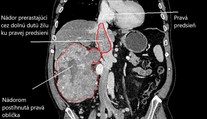

FOTO: Mal akoby dve hlavy. Mužovi odoperovali vzácny nádor gigantickej veľkosti Ľubomíra Ivanková 5. 3. 2024